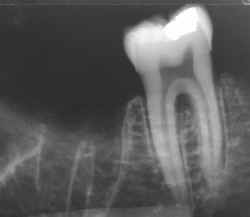

espaco2.gif (821 bytes)Radiografia do suspeito obtida intra-vitae e encaminhada ao IML pelo Cirurgião Dentista que cumpriu seu papel arquivando os exames complementares no prontuário odontológico.

espaco2.gif (821 bytes)Identificação positiva pela comparação computadorizada. Uma única radiografia intra-vitae como a comparada ao lado é suficiente para esta afirmação.